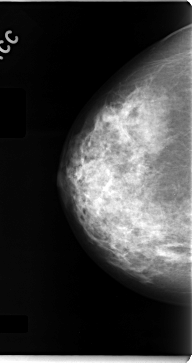

C_0062_1.RIGHT_CC

RIGHT_CC LINES 4712 PIXELS_PER_LINE 2488 BITS_PER_PIXEL 12 RESOLUTION 50 NON_OVERLAY

RIGHT_MLO LINES 4696 PIXELS_PER_LINE 2552 BITS_PER_PIXEL 12 RESOLUTION 50 NON_OVERLAY